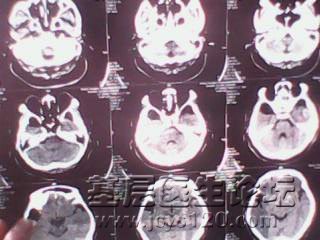

一列多发性脑梗塞市医院的治疗处方

[/font] [font=楷体][size=5][b][color=Red] 处方:<1>0.9%盐水250 注射用灯盏花素10mgx2支 <2>0.9%盐水250 银杏达莫注射液10mlx2支 一天一次 [/font]